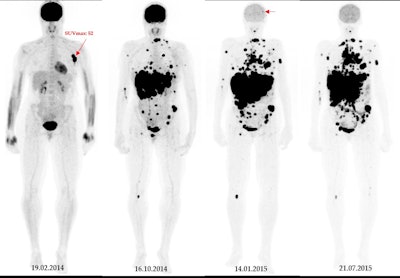

A 49-year-old patient with primary clinical stage III melanoma underwent F-18 FDG-PET. The primary tumor Breslow thickness was 6.5 mm. On initial F-18 FDG-PET images, this patient had a high SUVmax (52), resulting in limited survival with the occurrence of brain metastasis in the first year of follow-up (horizontal arrow). Notably, during the course of the treatment, the patient underwent surgical removal of the primary tumor as well as lymph node dissection, followed by neoadjuvant radiotherapy and immunotherapy. Image courtesy of Cancers.